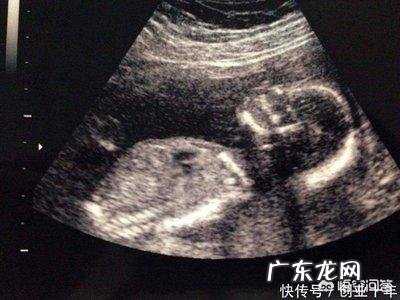

受精卵着床,说明你“中头奖”,怀孕成功了 。怀孕后,准妈妈的症状也各有不同 。